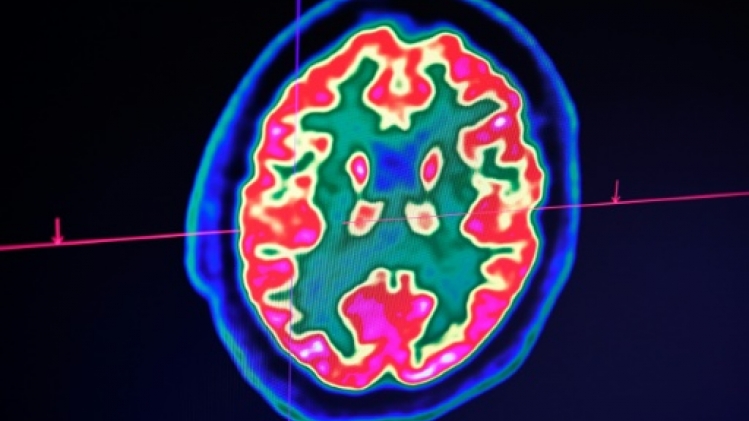

D'emblée, Lucas répond très bien au traitement. "Au fil des IRM, j'ai vu la tumeur complètement disparaître", raconte le Dr Grill, qui n'ose, malgré ces résultats miraculeux, décider d'arrêter le médicament. Jusqu'à ce qu'il comprenne, il y a un an et demi, que l'enfant avait lui-même cessé de le prendre.